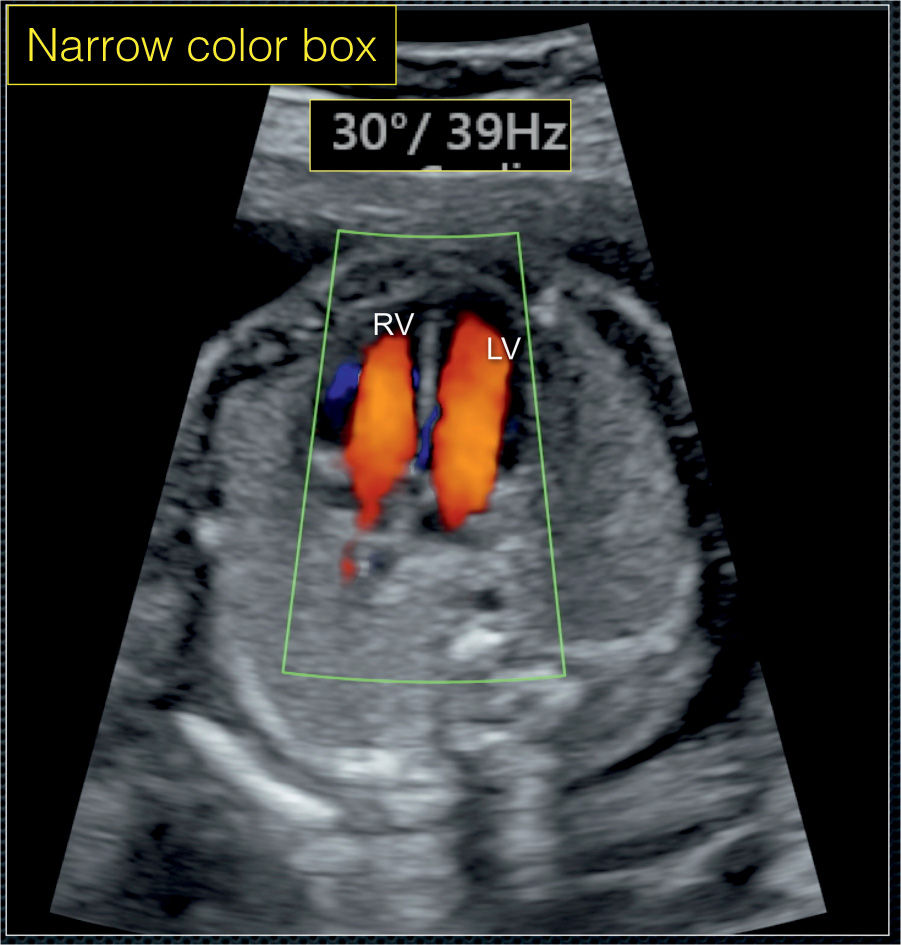

It is performed for the examination of the umbilical vessels located in the umbilical cord of the baby. High performance, low power consumption industrial control solution, to ensure better image. Blue represents that the blood flow is away from the probe and red represents that the blood flow is towards the probe.

Red means flow in one direction while blue means flow in the opposite direction. Ultrasound tell if baby is black or white. Color doppler is not part of the standard examination of the heart, but is used by a specialist with special training in fetal echocardiography. Your baby is also going to look either grey or white on the ultrasound.